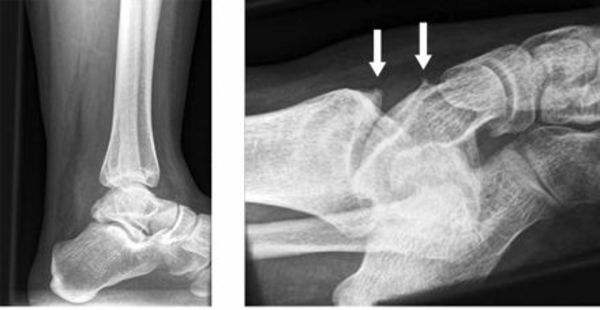

临床上,骨刺经常出现的位置是膝,腰,颈,足这些部位。都是日常承受重量比较多的地方。

如果骨刺在膝关节里,会引发关节卡压,产生“咔咔”的弹响声伴有摩擦感,产生肿胀疼痛,影响膝关节的伸直,影响日常行走,下蹲等活动。如果骨刺增生在颈椎,患者会感到脖子僵硬,疼痛,且如果压迫到椎动脉,患者就会出现头晕目眩,手麻,脚底踩棉花的症状;这就是颈椎病的一种。如果骨刺增生在腰椎,又严重到压迫了脊髓,就可能会出现身体僵硬、疼痛,红肿,下肢过电式疼痛。这时就表明骨质增生已经很严重,需要到医院寻求治疗了。